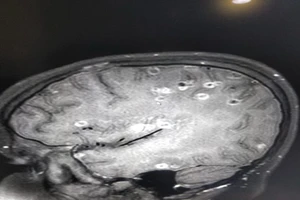

Kinh hoàng: Não bé 8 tuổi có 100 trứng sán dây

Bé trai 7 tuổi bị động kinh không ngờ do dị dạng mạch máu não